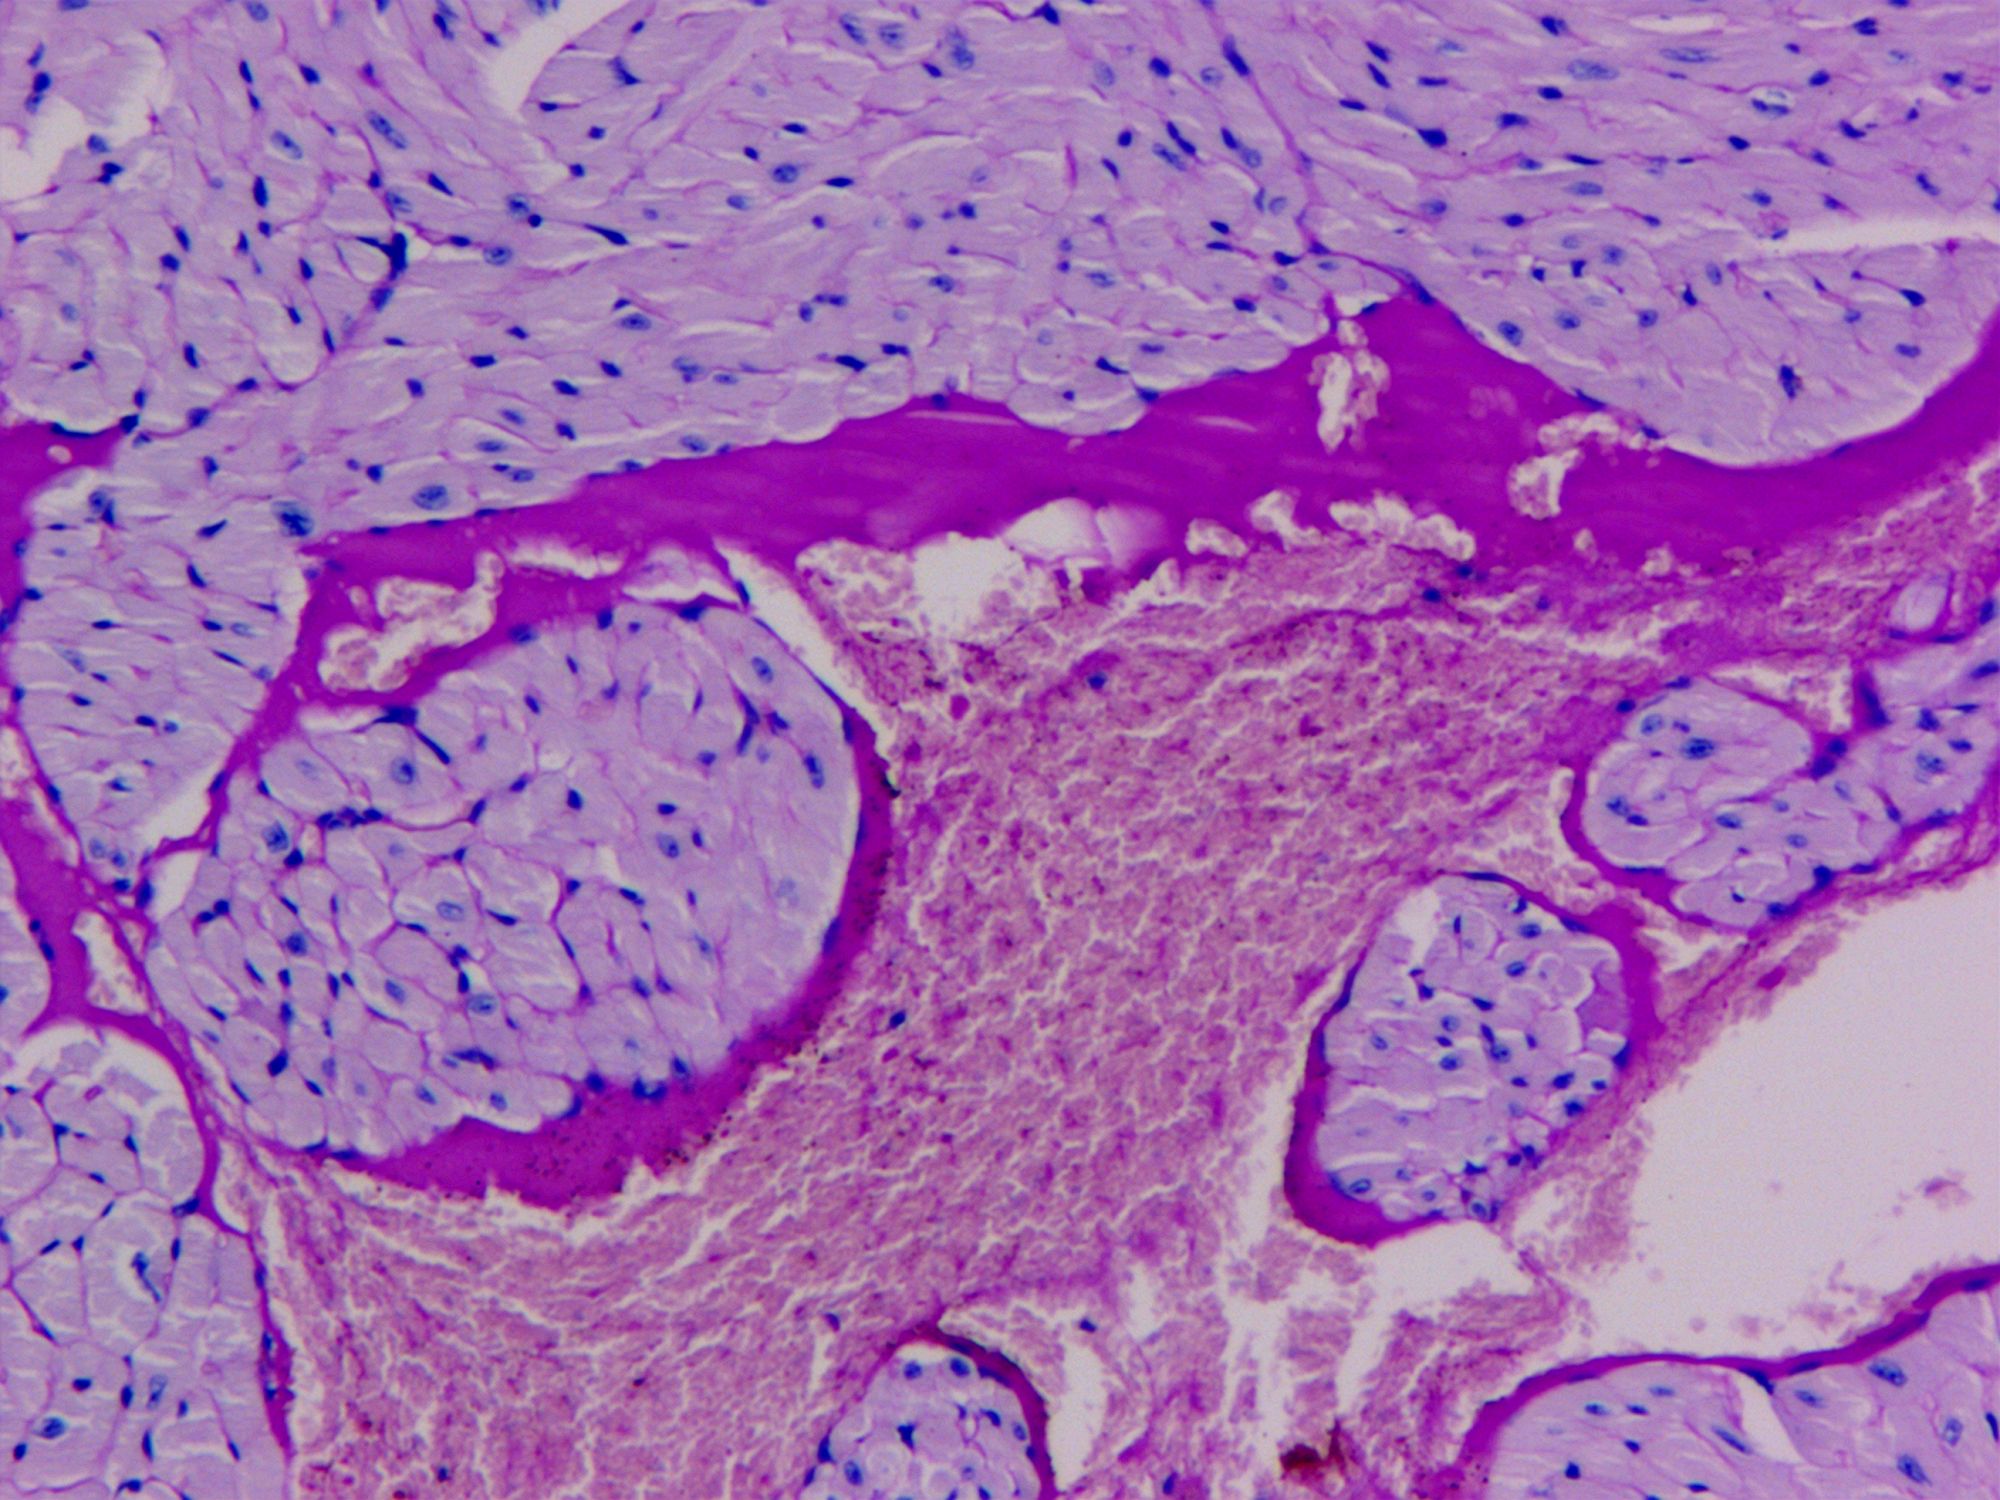

PAS染色法(Periodic Acid-Schiff stain)在組織學(xué)上,又稱過(guò)碘酸雪夫染色,糖原染色。一般用來(lái)顯示糖元和其它多糖物質(zhì),過(guò)碘酸把糖類相鄰兩個(gè)碳上的羥基氧化成醛基,再用Schiff試劑和醛基反應(yīng)使呈現(xiàn)紫紅色。

PAS染色糖原染色是病理學(xué)中常規(guī)的染色方法之一,氧化劑能氧化糖類及有關(guān)物質(zhì)中的1,2-乙二醇基,使之變?yōu)槎?,醛與Schiff試劑能結(jié)合成一種品紅化合物,產(chǎn)生紫紅色。PAS技術(shù)常用來(lái)顯示糖原和其他多糖,該染色液不僅能夠顯示糖原,還能顯示中性黏液性物質(zhì)和某些酸性物質(zhì),以及軟骨、垂體、霉菌、真菌、色素、淀粉樣物質(zhì)、基底膜等。

PAS反應(yīng)陽(yáng)性物質(zhì) 紅色或紫紅色

細(xì)胞核 藍(lán)色

細(xì)胞質(zhì) 深淺不一的紅色